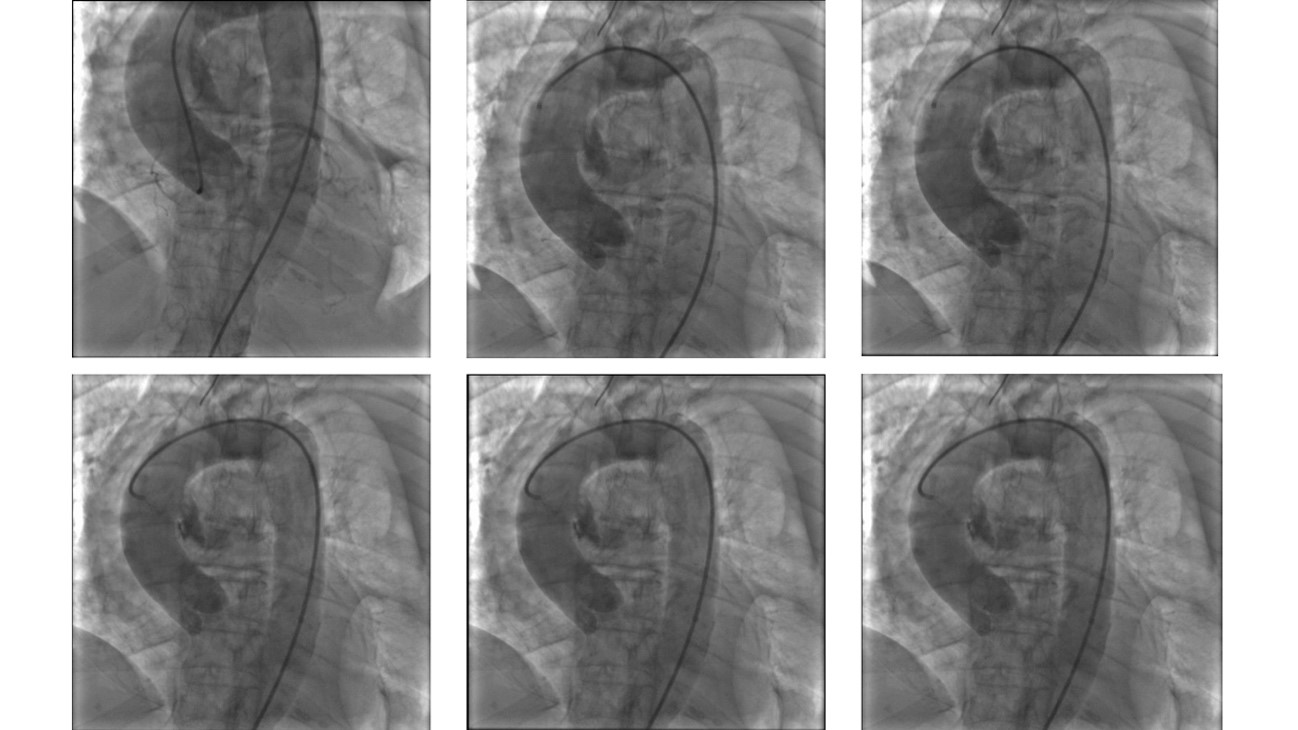

After 2 cycles of standard cardiopulmonary resuscitation (CPR), without any apparent rib or sternal fractures, return of spontaneous circulation was achieved and then followed by emergency coronary angiography. No epicardial coronary significant lesions were found, but an unexpected ascending aortic wall rupture was surprisingly noticed, with a clear movable flap and contained dye extravasation (Figure 2; Videos 1-3). Just after the fast angiograms, there was recurrence of pulseless electrical activity. Despite advanced cardiovascular life support, sustained return of spontaneous circulation was not achieved after more than 30 minutes of CPR, thus precluding any complementary imaging modality evaluation and ultimately the mandatory aortic rupture surgical correction.